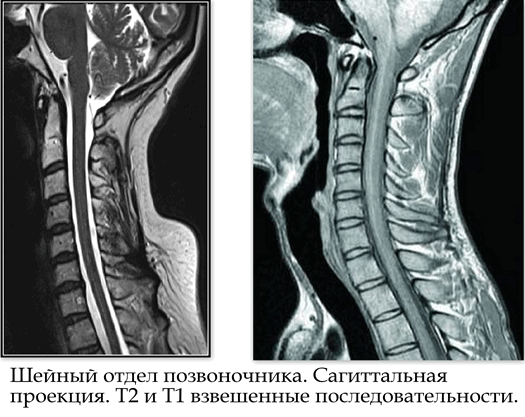

Результаты МРТ при исследовании шейного отдела позвоночника.

Результаты МРТ шейного отдела позвоночника в большинстве случаев аналогичны результатам МРТ позвоночника в целом. Среди особенностей МР-томографии шейного отдела можно выделить: 1. выявления аномалий развития атланто-окципитального сочленения; 2. определение аномалий атланто-аксиального сочленения; 3. изменение физиологического лордоза шейного отдела; 4. выявление аномалий развития и прохождения брахиоцефальных артерий шейного отдела позвоночника при проведении МР-ангиографии (исследование артерий шеи).

Почти в каждой клинике используются свои протоколы МР-исследования позвоночника, это зависит от аппаратуры и от предпочтений самого врача. Однако существует определенный минимум набора программ, который необходимо выполнить. Это исследования в сагиттальной проекции – вертикальные срезы вдоль оси позвоночного столба, выполненные в Т1 и Т2 взвешенных последовательностях, а также в аксиальной проекции – при помощи Т2 взвешенной последовательности. При необходимости стандартный протокол исследования может дополняться исследованием в корональной (фронтальной) проекции, а также последовательностью с подавлением сигнала от жировой ткани в любой из трех проекций. Кроме того, область особого интереса, выявляемая при МР-исследовании, для детального осмотра может быть визуализирована при помощи программ с максимально тонкими срезами. Анализ снимков проводит радиолог (рентгенолог): врач, который специализируется на проведении радиологических исследований и интерпретации полученных результатов. После изучения снимков врач-специалист составляет и подписывает заключение, которое предоставляется лечащему врачу. В некоторых случаях заключение можно забрать у самого врача-рентгенолога. Часто требуется последующее дообследование, точную причину проведения которого пациенту объяснит лечащий врач. В некоторых случаях дообследование проводится при получении неясных результатов, которые требуют разъяснения в ходе повторного исследования с применением особых методик визуализации. Динамическое наблюдение с помощью МРТ позволяет вовремя выявить какие-либо патологические состояния, возникающие со временем. Также в ходе обследования, либо при динамическом контрольном обследовании врач может предложить пациенту дополнительное обследование с контрастным усилением – это подразумевает внутривенное введение раствора контрастного парамагнитного вещества специально предназначенного для исследований в магнитно-резонансной томографии. Это необходимо при обследовании онкологических пациентов, а также больных с воспалительными или инфекционными процессами, либо для оценки динамики выявленных патологических процессов и контроля эффективности выполненного оперативного вмешательства. Во многих ситуациях повторное обследование позволяет говорить об эффективности проведенного лечения или стабилизации состояния со временем.